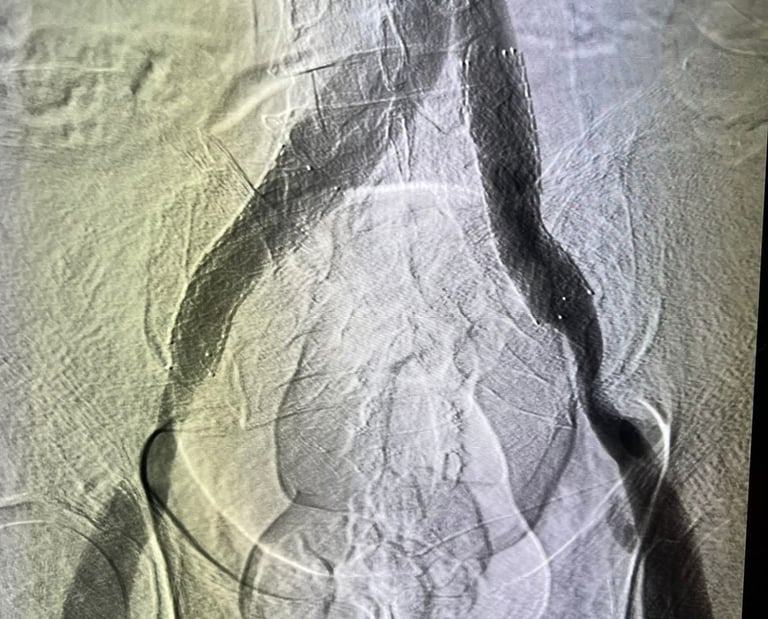

Flebografía (Cateterismo)

Procedimientos mínimamente invasivos realizados a través de punciones en las venas. Con el uso de dispositivos especiales, como catéteres, ultrasonido, stents y sistemas para la infusión de medicamentos, se busca tratar venas afectadas por cicatrices y trombosis. Estos procedimientos permiten mejorar el flujo venoso y, en casos de trombosis venosa profunda, extraer los coágulos para prevenir complicaciones graves.